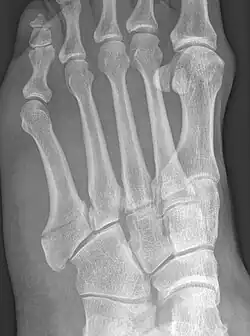

The Jones fracture

Robert Jones described the fracture of the fifth metatarsal which bears his name in the Annals of Surgery in 1902. In his paper, Jones described the fracture in a series of six patients, the first of which was himself.[8] He had injured his foot while dancing several months earlier, and had thought the injury to be to a tendon in the foot. He examined himself the day after the injury, and found that the tendon was intact, but he could not find definite evidence of bony injury. He asked a colleague, David Morgan, to X-ray his foot, and a fracture above the base of the fifth metatarsal was found. The finding of similar fractures in several patients after his own prompted him to write about it. He also noted that the fracture was not caused by direct trauma to the bone, as had always been assumed before, but by a cross-strain being applied to the bone.[9]